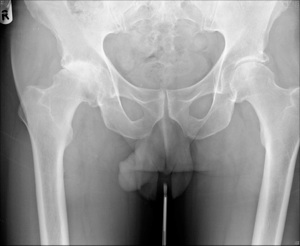

hip resurfacing

The first hip resurfacing was implanted in 1991. It was designed for younger more active patients by Mr Derek McMinn at the Royal Orthopaedic Hospital, Birmingham. It is a more complex procedure compared to a routine hip replacement and should be performed by a specialist hip surgeon. It involves replacing the ball of the hip joint without placing a long stem down the centre of the femur ( like a traditional hip replacement).

There are a number of advantages of hip resurfacing. Patients tend to rehabilitate and recover faster compared to routine hip replacement patients. They also generally return to a higher activity level. Hip Resurfacing preserves more bone in the femur for future replacement operations. It has a metal on metal bearing surface which has excellent wear properties compared to traditional hip replacements. The large femoral head size has been reported to reduce the risk of dislocation.